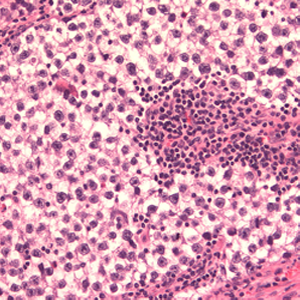

Bildeeksempler:

Germinalcellesvulst

Seminom

Germinalcellesvulst som er bygget opp av ensartete celler med lyst eller tett glykogenholdig cytoplasma med stor regelmessig kjerne, med en eller flere kjernelegemer og tydelige cellegrenser. Seminomer utgjør cirka 50 % av alle germinalcellesvulster i testikkelen. Den forkommer uhyre sjelden hos barn, ungdommer eller hos pasienter over 70 år.